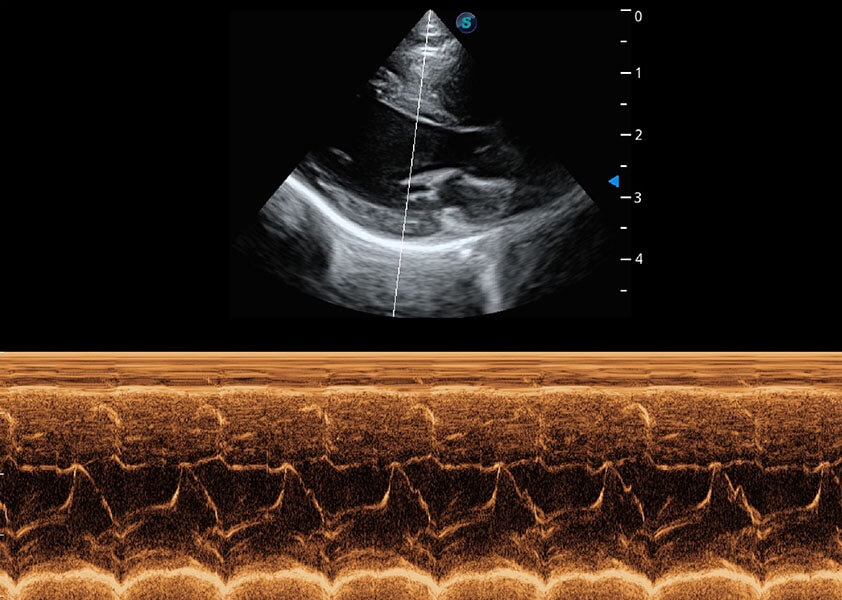

心脏解决方案

ProPet 60 配备了丰富的心脏探头群、先进的成像技术和专业的心脏测量工具,可帮助动物医生为不同体型和生理结构的动物提供心脏和心肌功能的全面评估。

• AMM 解剖M型

通过360度任意调节3条M型取样线,在同一心动周期上观察心脏不同位置的运动曲线,得到准确的心功能测量数据,有效评估心肌运动及左心室功能。

(犬)乳头肌短轴

(猫)二尖瓣M型